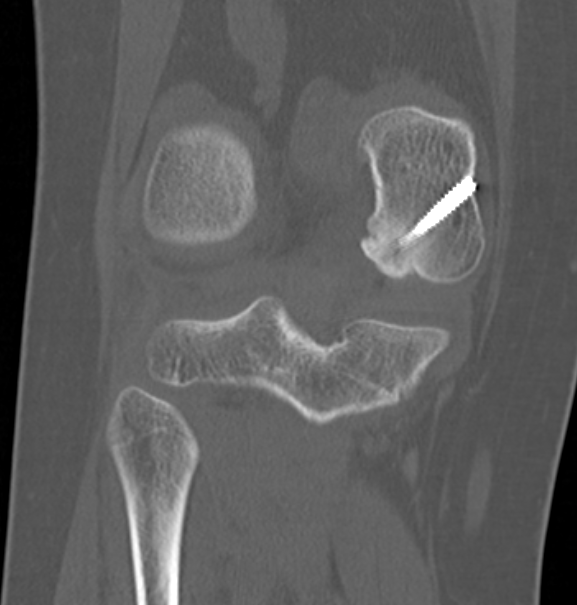

MFC unstable OCD

LFC unstable OCD